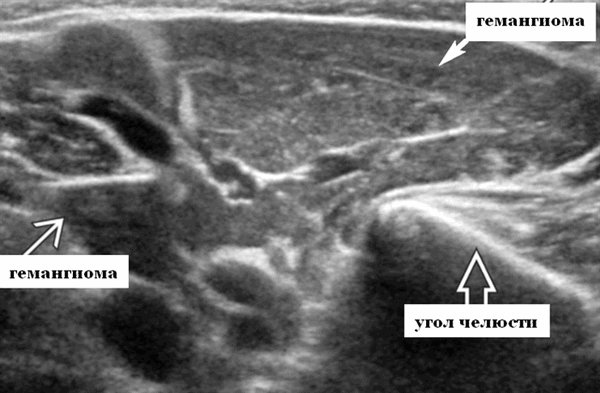

Лучшая диагностическая подсказка. Четко выраженная опухоль с диффузной гиперваскуляризацией внутри очага поражения / интенсивным усилением кровотока на УЗИ с ЦДК. Сосуды внутри и рядом с образованием во время фазы пролиферации (ФП). Уменьшение размера за счет замещения жировой ткани во время фазы инволюции (ФИ)

Серошкальное УЗИ. Четко выраженная солидная некальцинированная опухоль мягких тканей. Однородная картина эхоструктуры. ПФ: Гипоэхогенный вид по сравнению с паренхимой околоушной железы; ИФ: эхоструктура от изо- до умеренно гиперэхогенной